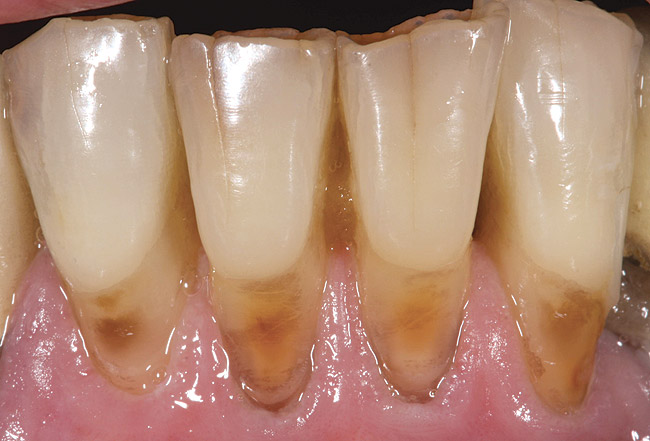

Stage 3 Demineralization (D3)

Most practitioners are currently taught to diagnose a D3 root-surface lesion (Figure 4) as active caries. The root surface is soft, sticky, cavitated, and may have debris that is easily removed with gentle palpation with the side of the explorer. Color changes may range from yellow orange/light brown to dark brown/black. The recommended treatment for D3 root-surface lesions includes remineralization of the root surface with products (pastes and varnishes) containing fluoride, calcium, and phosphate and subsequent restoration of the lost root-surface structure.

It is the experience of the authors that remineralization therapy applied to D3 root surfaces has the potential to result in root surfaces that, although discolored and cavitated, are completely hardened to a glassy, shiny surface. This allows the practitioner to preserve tooth structure that would otherwise be removed during preparation and provide a minimally invasive restoration. In cases where there is minimal cavitation in non-esthetic areas, the practitioner may opt to monitor the root surface for further change instead of placing a restoration. This classification system will aid the practitioner in diagnosing and monitoring these root surfaces.

Figure 4  This root surface is black and cavitated. When exploring with the side of the explorer, this root surface will feel soft and sticky, and it may be possible to remove soft debris from this lesion.

Figure 4